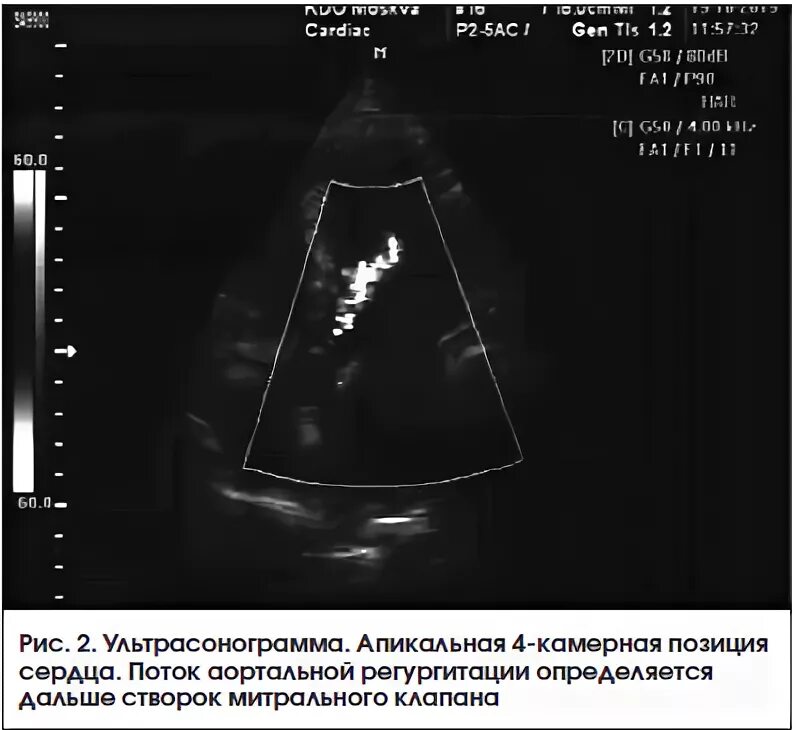

Уплотнение стенок аорты сердца на узи что